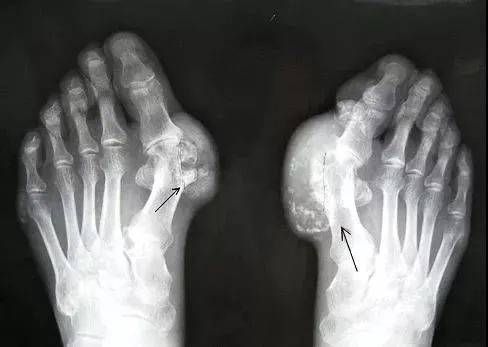

所谓痛风

是由尿酸盐沉积导致的

一种晶体相关性关节病

痛风的病因是「高尿酸血症」

就好比水里的盐浓度太高了

慢慢被析出来就形成“尿酸结晶”导致痛风

痛风性关节炎急性发病期

受累关节会发热、变得暗红、肿胀

感觉有刀割或咬噬样疼痛